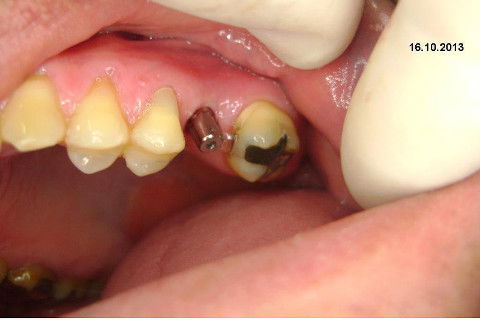

Instalação de um implante em região do 26. Utilizamos um implante cone morse Alvim Neodent 4.3 X 11,5. Foi uma cirurgia muito rápída e minimamente traumática, sem retalho e sutura.